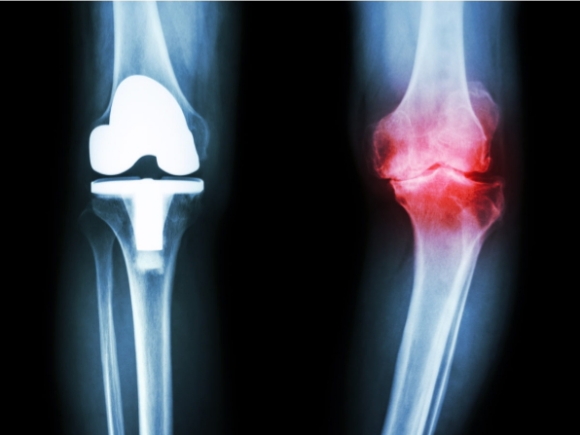

If your doctor wants to treat the osteoarthritis in the knee with surgery, the options are arthroscopy, osteotomy, and arthroplasty.

- Joint replacement surgery, or arthroplasty, is a surgical procedure in which joints are replaced with artificial parts made from metals or plastic. The replacement could involve one side of the knee or the entire knee. Joint replacement surgery is usually reserved for people over age 50 with severe osteoarthritis. The surgery may need to be repeated later if the prosthetic joint wears out after several years. But with today’s modern advancements, most new joints will last over 20 years. The surgery has risks, but the results are generally very good.